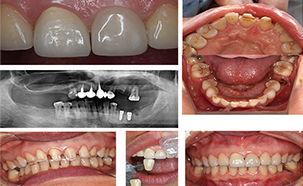

主页>種牙案例>种植案例